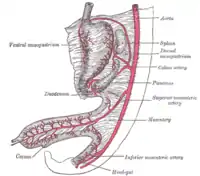

Tronco celíaco con sus ramas. El tronco celíaco es visible en el centro. | ||

Ramificándose desde la aorta a la altura de la parte superior de la vértebra L1 (o primera lumbar), por debajo del diafragma, en los seres humanos, es una de tres ramas que desde la línea media se proyectan hacia adelante —las otras dos son la mesentérica superior y la mesentérica inferior—. Ocupa el centro de la denominada región celíaca.

Existen tres divisiones principales de la arteria celíaca (arterias: gástrica izquierda, esplénica y hepática común). A continuación se muestra la arteria celíaca con sus sucesivas ramas, las ramas de aquellas y sus respectivas anastomosis.[2]

La arteria celíaca proporciona sangre oxigenada al hígado, estómago, parte abdominal del esófago, bazo y la mitad superior del duodeno y del páncreas. Estas estructuras corresponden al intestino proximal embrionario. (De igual modo, las arterias mesentérica superior y mesentérica inferior irrigan estructuras que se desarrollaron del intestino medio e intestino distal, respectivamente. Nótese que estas tres ramas anteriores de la aorta abdominal son diferentes y no pueden sustituirse, aunque existen conexiones limitadas entre sus ramas terminales).